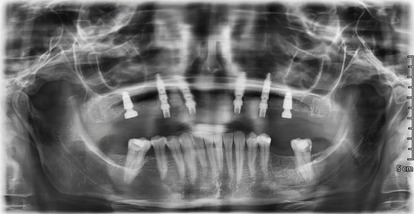

La paziente si è presentata alla nostra osservazione con una dentatura dell’arcata superiore gravemente compromessa, caratterizzata da carie destruenti, fratture radicolari, elementi non recuperabili e una funzionalità ormai insufficiente sia dal punto di vista masticatorio che estetico (Fig. 1). Si è discusso delle alternative di cura con la paziente, con una analisi delle proposte terapeutiche, in base a collaborazione e capacità economica espresse dal paziente. Dopo un’accurata valutazione clinica, fotografica e radiografica, è stato concordato un percorso di riabilitazione totale su impianti, basato su pianificazione digitale al fine di garantire massima precisione, sicurezza e predicibilità.

Il trattamento ha previsto l’inserimento di impianti Advan GTB TZERO secondo protocollo ATiM, selezionato per la sua affidabilità in situazioni anatomiche complesse, e l’utilizzo della componente protesica GFA, ideale per ottenere una corretta emergenza e una passivazione protesica ottimale. Il workflow interamente digitale ha consentito il matching accurato tra CBCT e scansioni intraorali, la progettazione della dima chirurgica e la gestione della fase protesica immediata, riducendo i tempi e aumentando il comfort della paziente. Il presente case report descrive in modo dettagliato tutte le fasi del trattamento –diagnostica, chirurgia e protesi – e documenta l’evoluzione clinica fino al follow-up, evidenziando come l’integrazione tra protocollo chirurgico Advan e tecnologie digitali possa migliorare significativamente prevedibilità, estetica e qualità di vita del paziente.